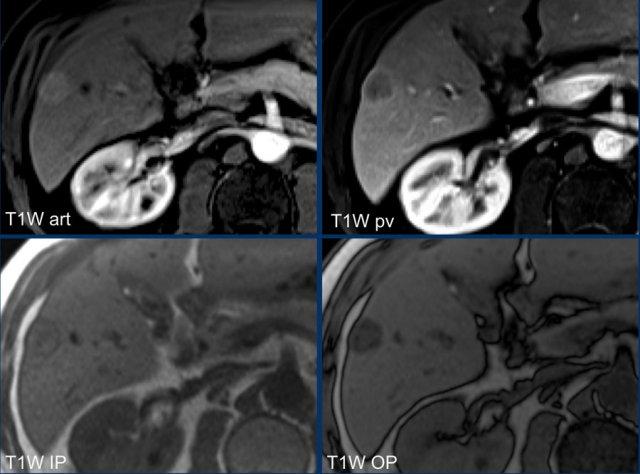

Hãy phân tích các hình ảnh MRI.

Các dấu hiệu hình ảnh là gì?

Các dấu hiệu ghi nhận được:

- Tăng ngấm thuốc thì động mạch không dạng viền (non-rim APHE) ở phân thùy VI của gan

- Thải thuốc ở thì tĩnh mạch cửa

- Vỏ bao ngấm thuốc

- Mỡ vi thể trên chuỗi xung đồng pha/ngược pha (IP/OOP)

Tiếp tục với hình ảnh tiếp theo…

Dựa trên các dấu hiệu hình ảnh trình bày ở trên, tổn thương được phân loại là LI-RADS 5 vì kích thước lớn hơn 20mm và có biểu hiện tăng ngấm thuốc, thải thuốc kèm vỏ bao.

Các đặc điểm bổ trợ ủng hộ chẩn đoán HCC bao gồm mỡ nội bào trên hình ảnh đồng pha/ngược pha (IP/OOP) và hạn chế khuếch tán.

Lúc này không thể nâng phân loại cao hơn LI-RADS 5, nhưng các đặc điểm bổ sung này sẽ giúp tăng thêm độ tin cậy cho chẩn đoán.